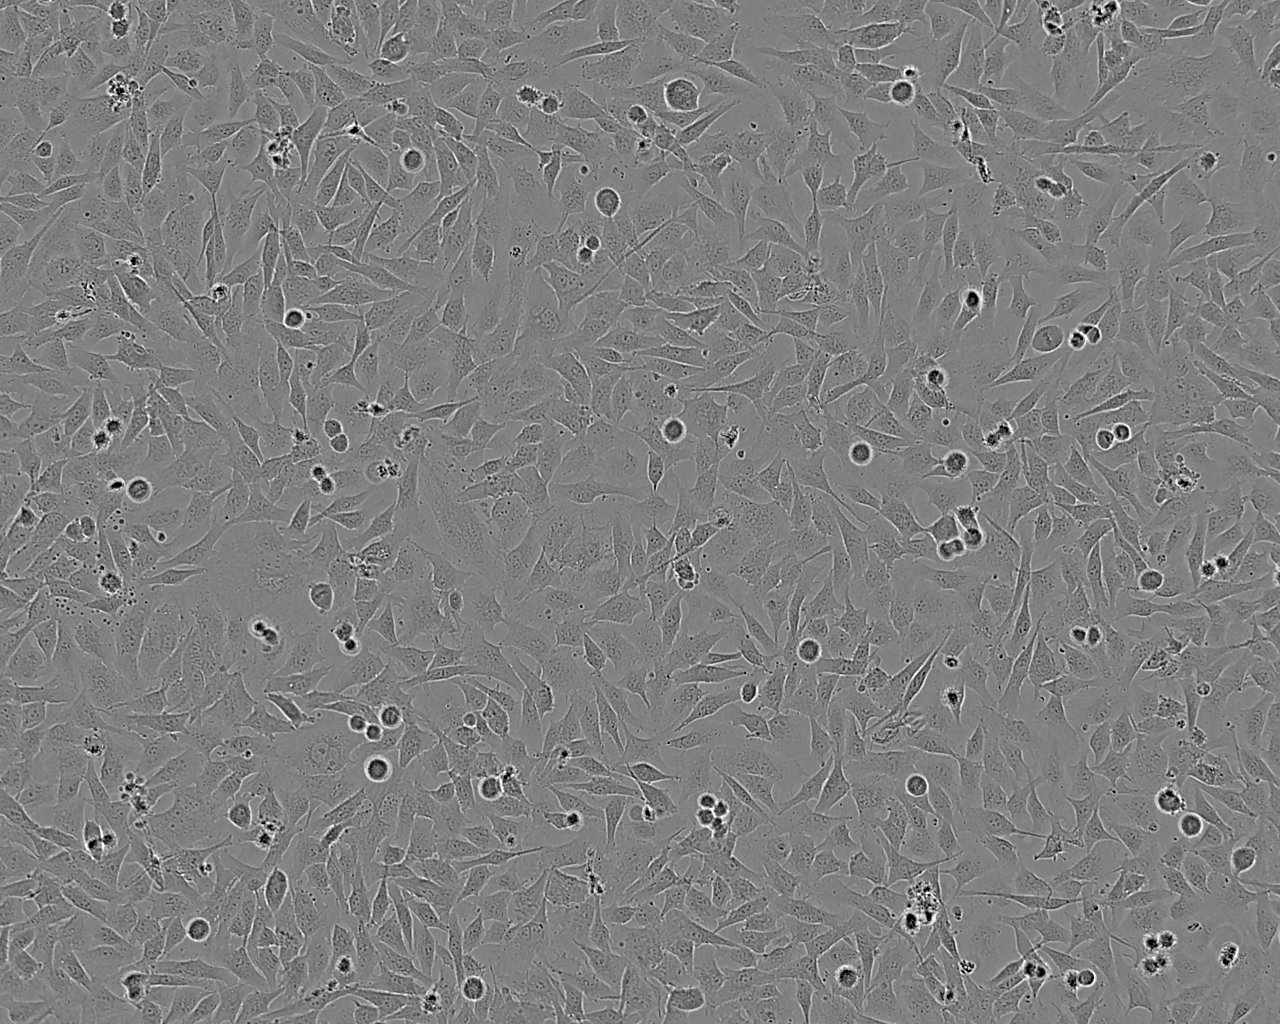

Derived from a subcutaneous nodule of a tumour from a 14-year-old male. Cells display remarkable blebbing.COLO 800 and COLO 794 (ECACC Catalogue number 94072237) were both derived from the same 14 year old male This has been confirmed by STR profiling.

Fibroblastic

Adherent